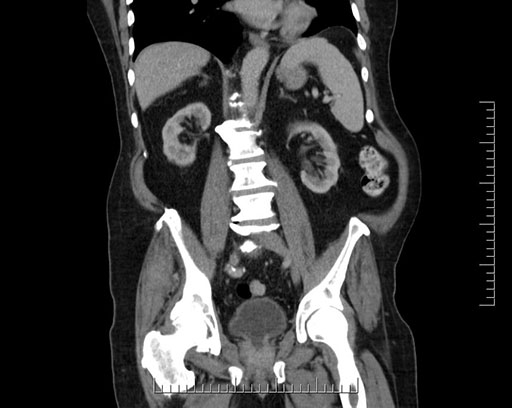

Imaging Analysis

Look through the patient's CT scan to identify any areas of concern for the necessary procedure.

Based on your CT findings, which issue(s) would give reason for "planned slowing down moment(s)" in this case?